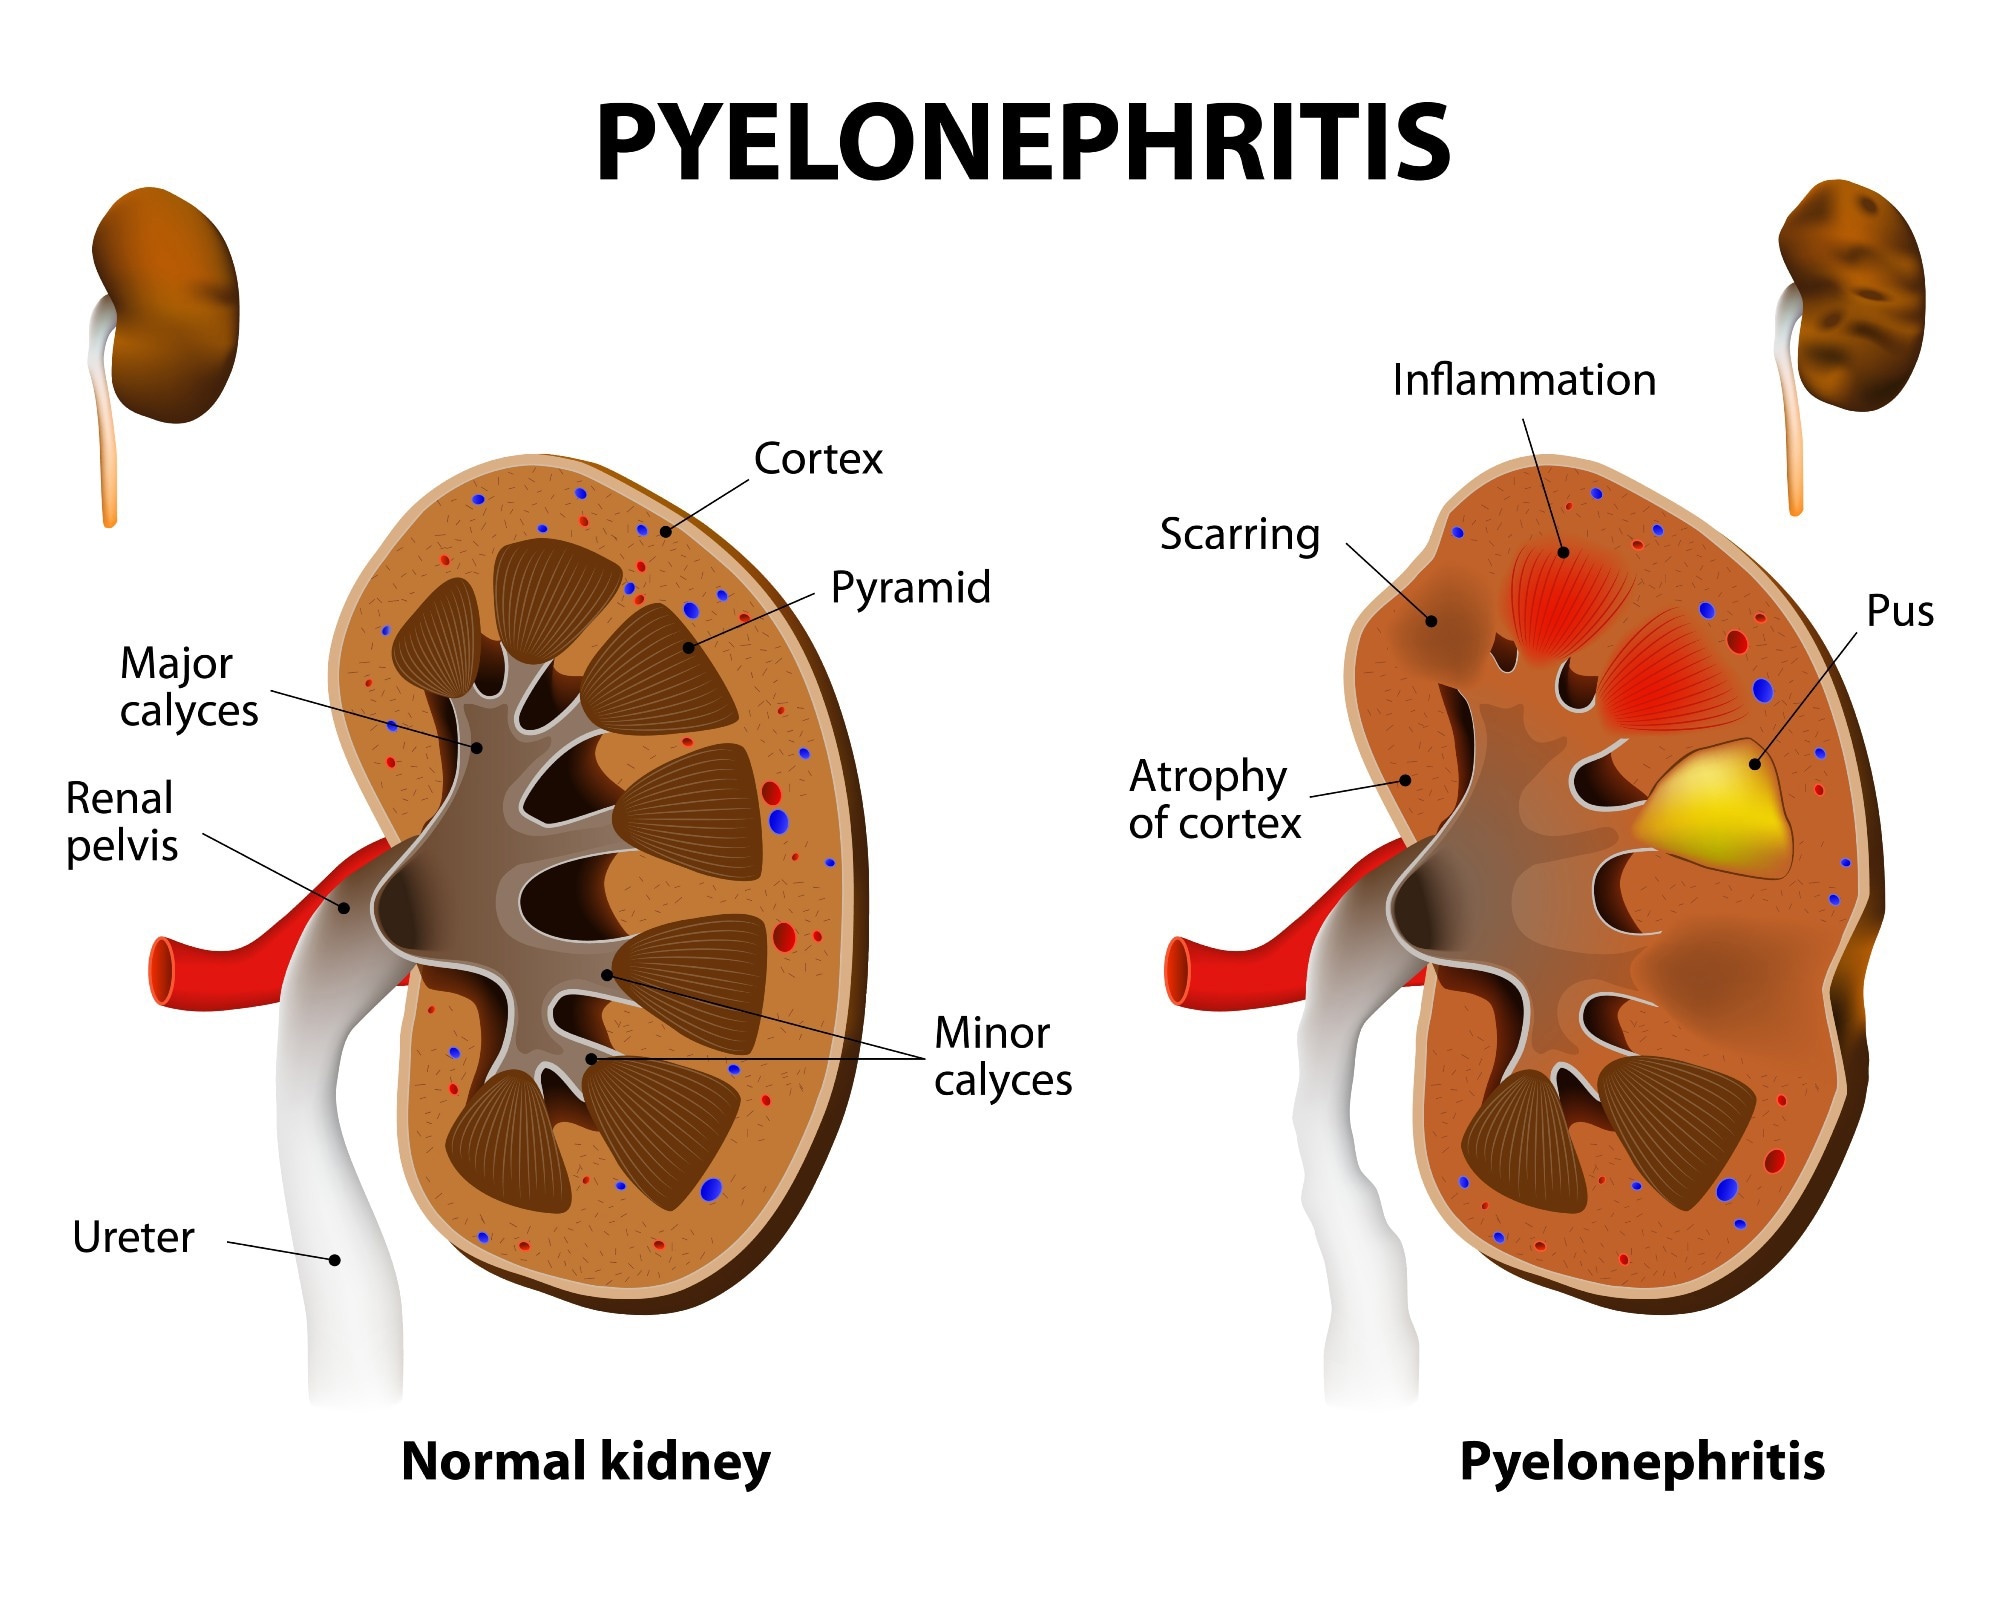

Симптомы подострого гломерулонефрита: фото и описание